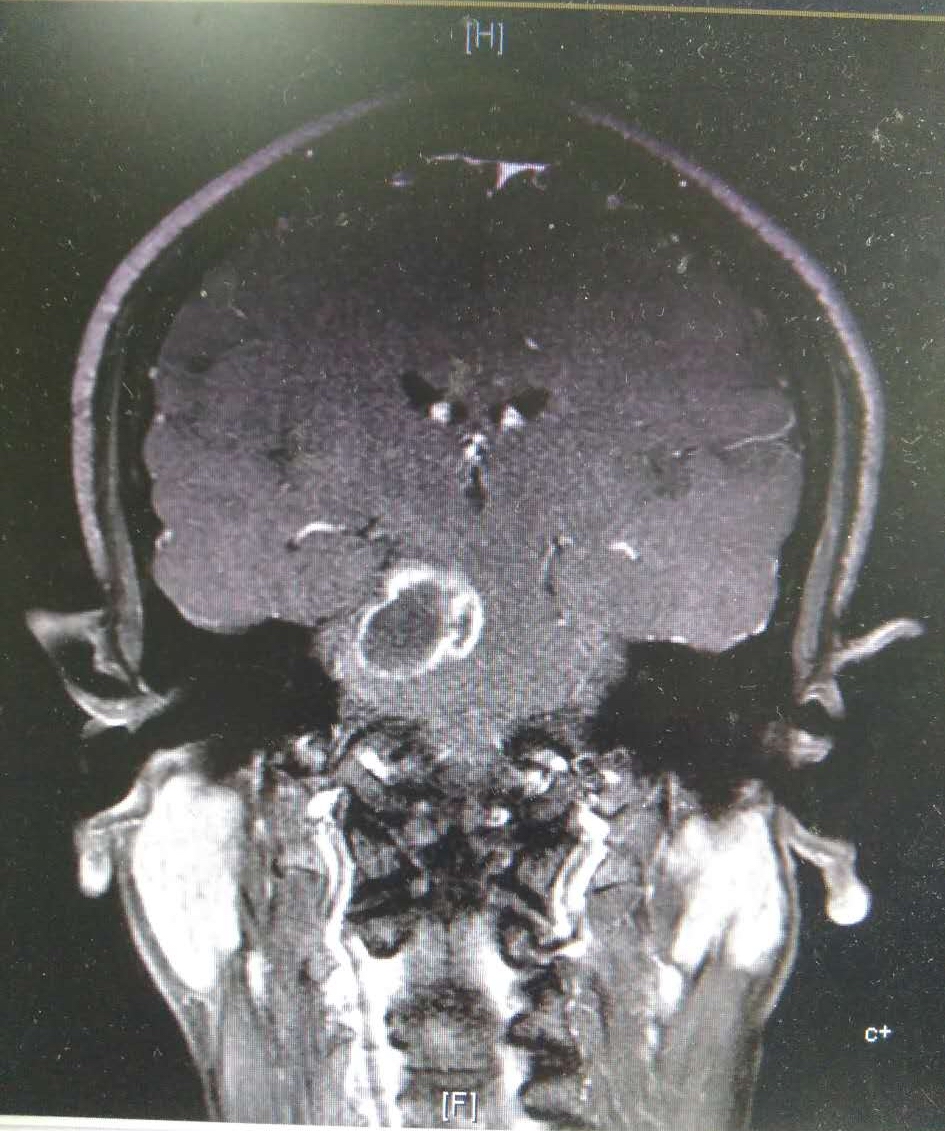

术前MRI肿瘤累及脑桥桥臂